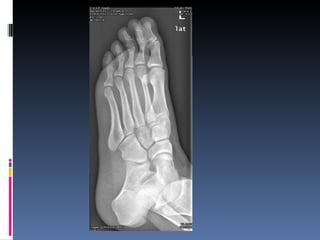

Abordaje de las Artritis Tejidos blandos  (edema, calcificacion) Densidad osea  Espacios articulares Erosiones Nuevo hueso  (osteofitos, periostitis) Patron Simetria

Abordaje de las Artritis Osteoartritis Artritis erosiva Artritis reumatoide Artritis psoriasica Gota Artritis infecciosa